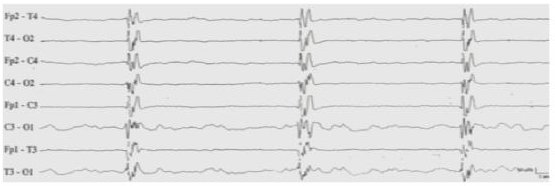

Figure 1: Suppression-Bursts EEG: recurrent generalized epileptic discharges followed by diffuse flattening.

figure 1